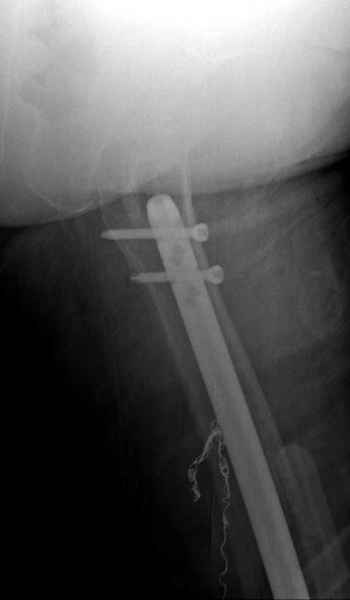

С минимальным рассверливанием и ретроградным методом провели остеосинтез бедра 12 мм гвоздем. (17-20)

Кровопотеря во время операции меньше 100 мл.